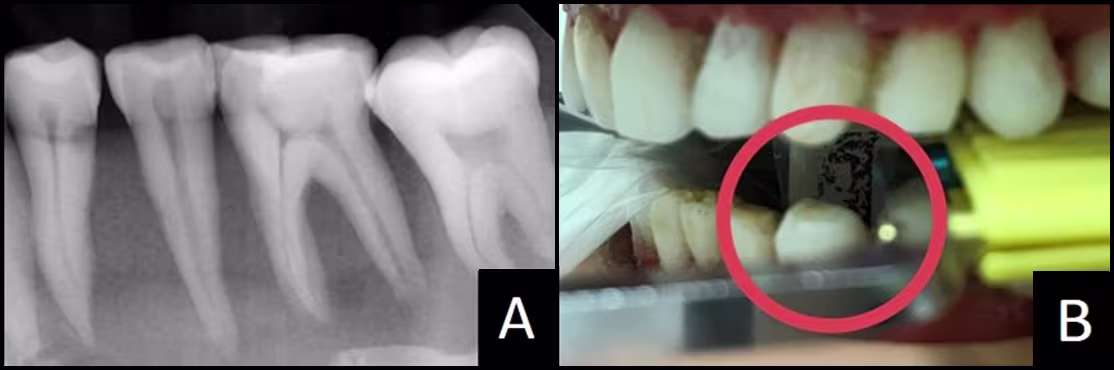

Figure 10 - Premolar Periapical

(A) Image without required distal crown #22.

(B) Deadzone behind #22 within red circle... tooth will not appear on the image.